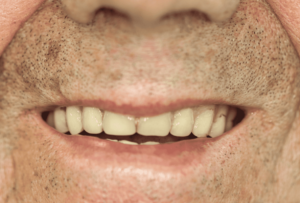

Caso de éxito 1